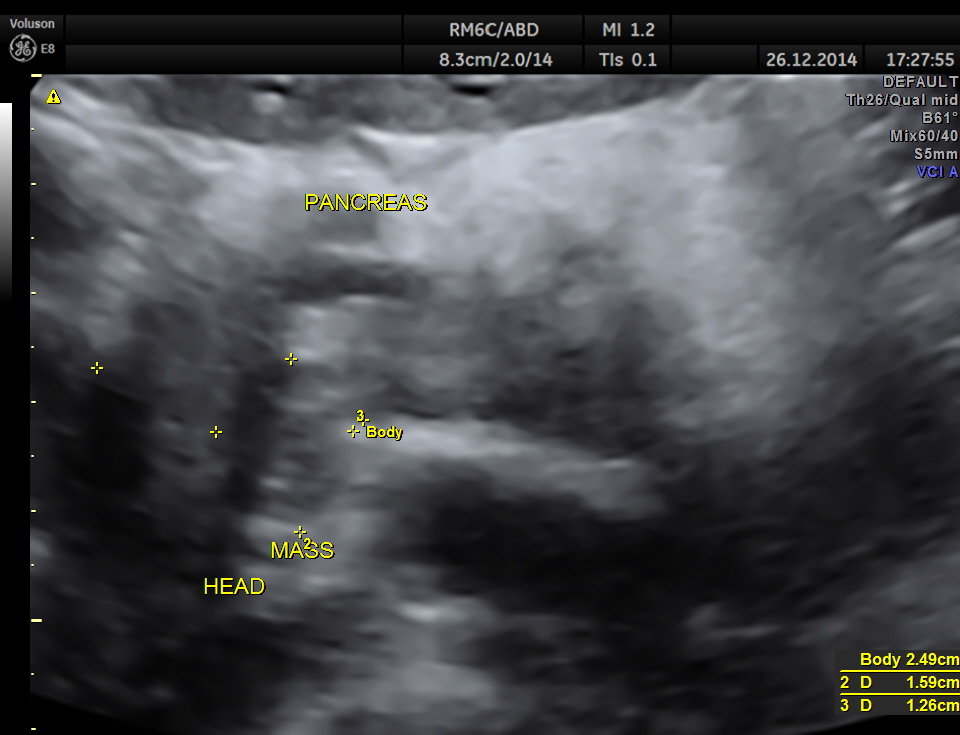

the head region of the pancreas shows an irregular mass lesion

3d reconstruction of the head of the pancreas

volume contrast image – A plane image of the pancreas